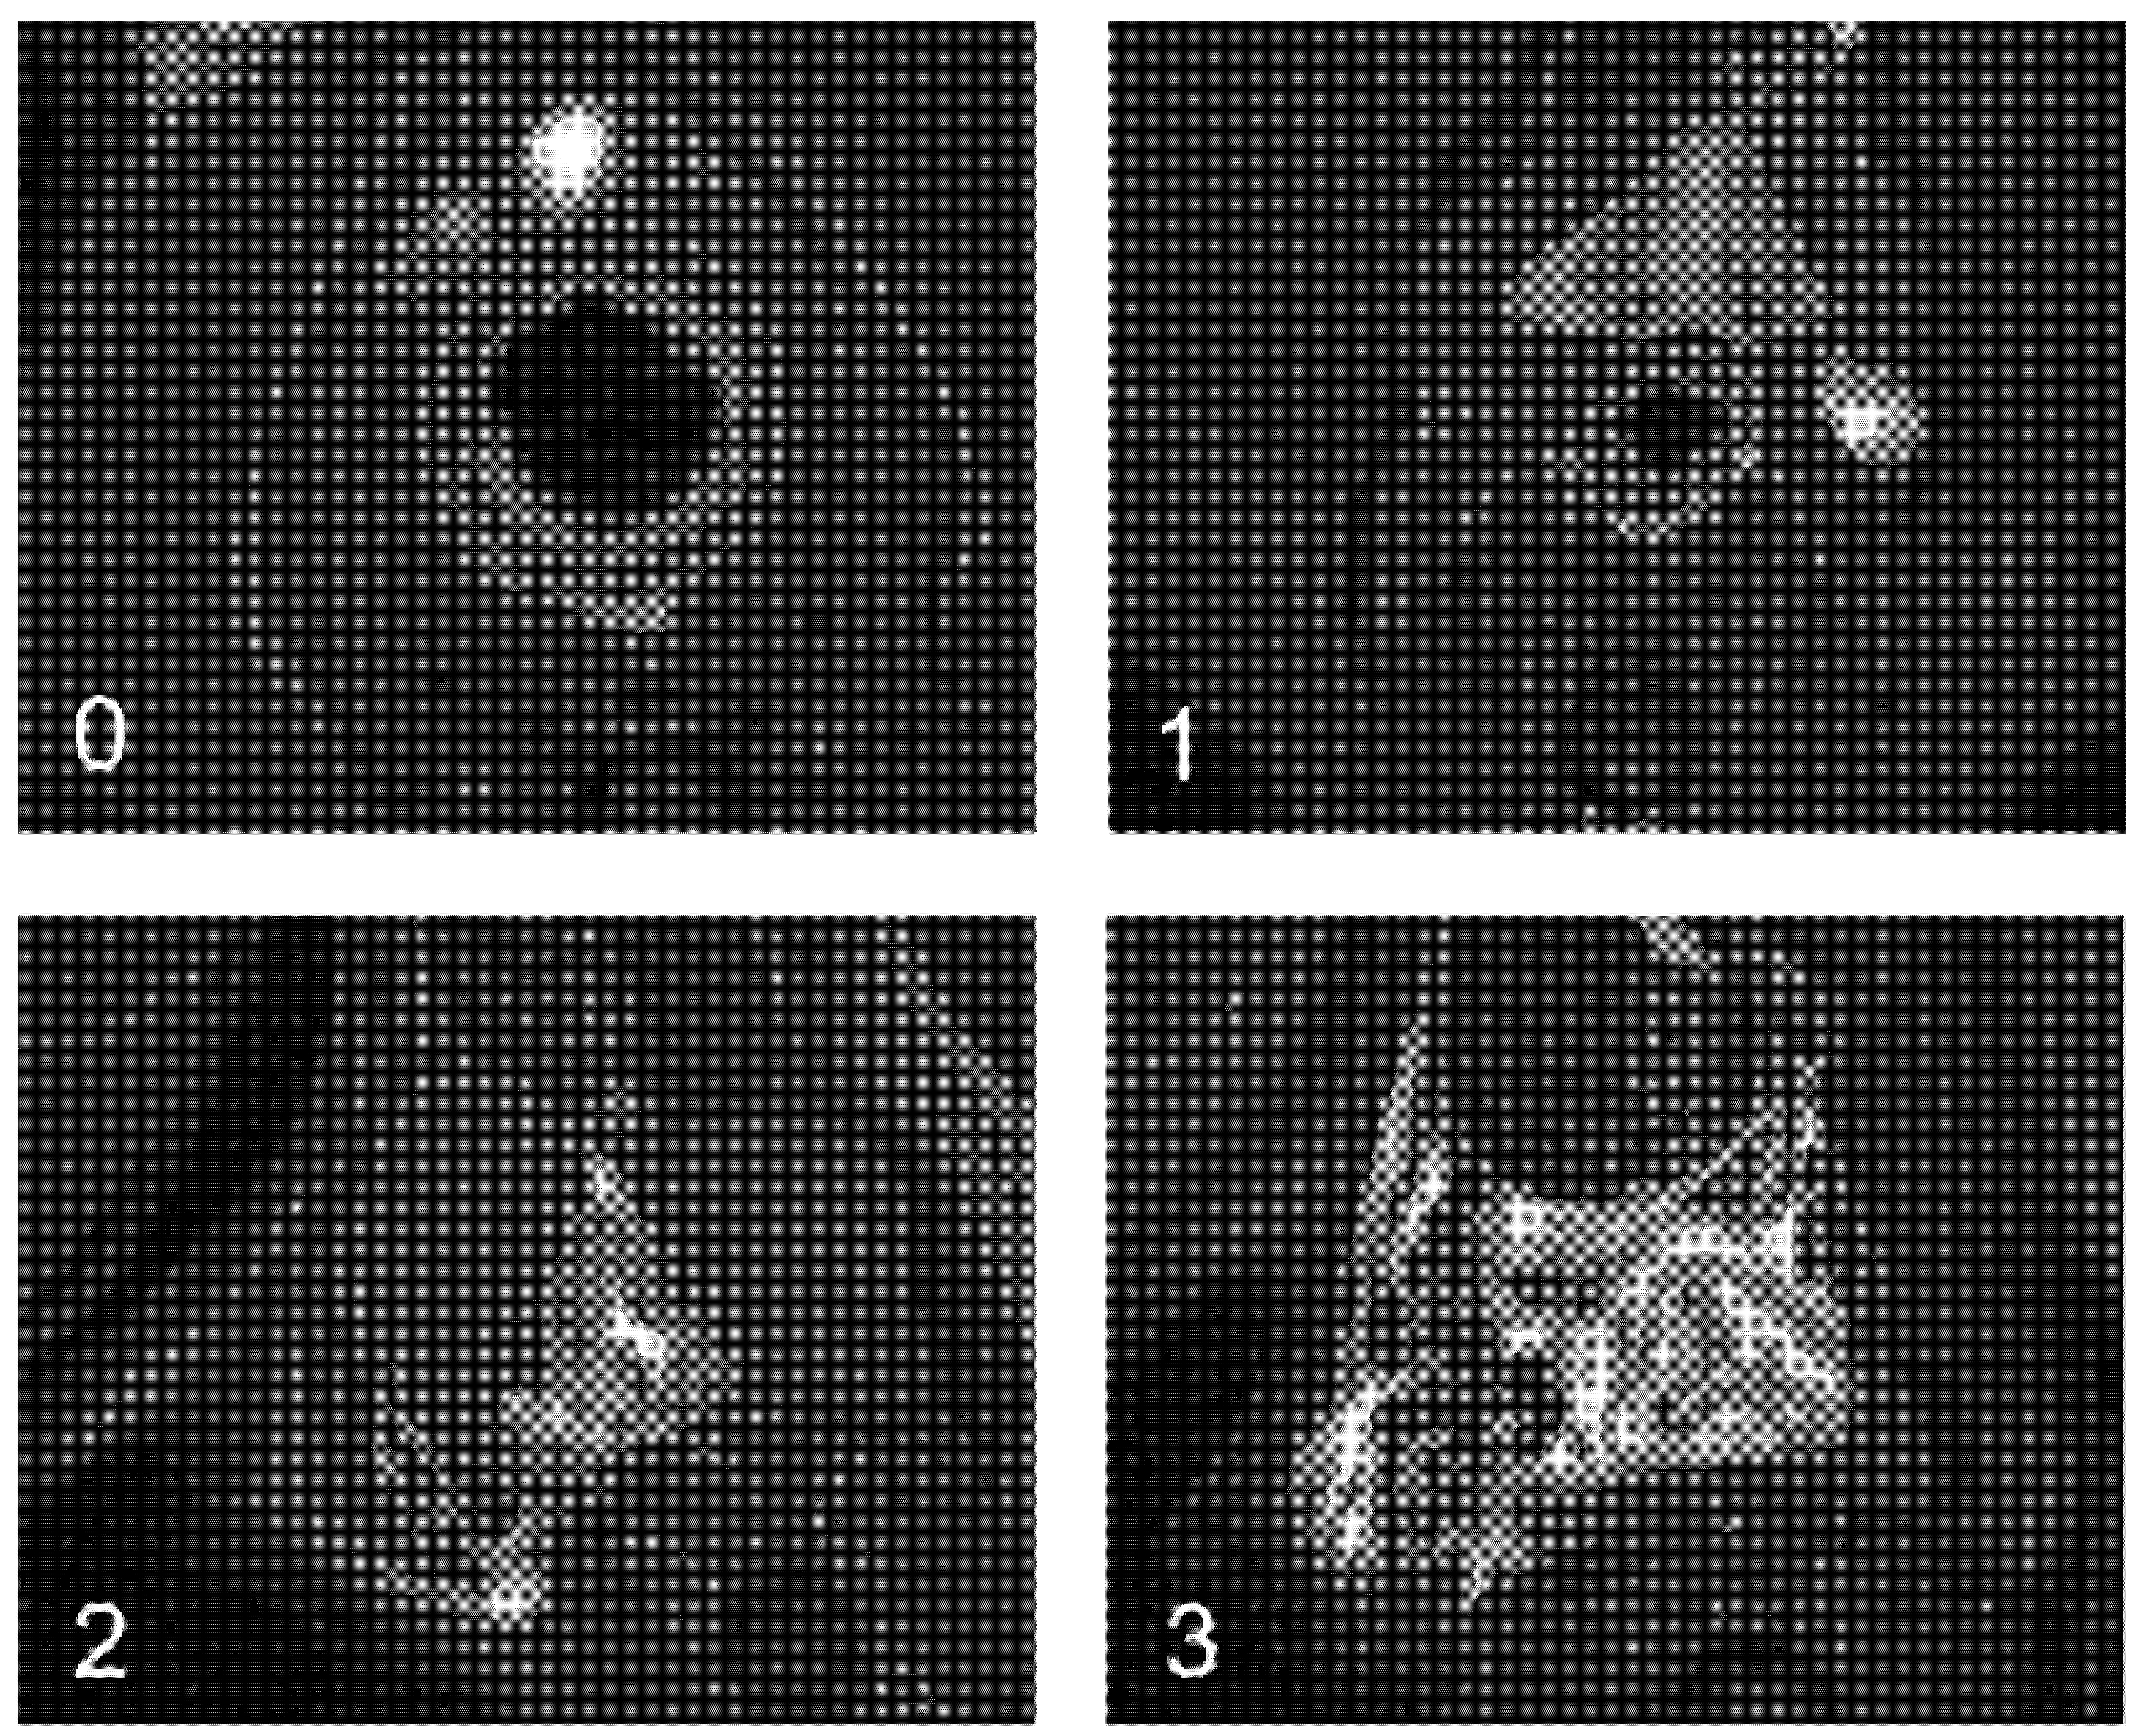

- day 35, baseline MRI: after maintaining the threads for 28 days, 2 inflammatory fistulas were obtained (Figure 6A) and a perineal MRI was performed to assess the pre-treatment tracts.